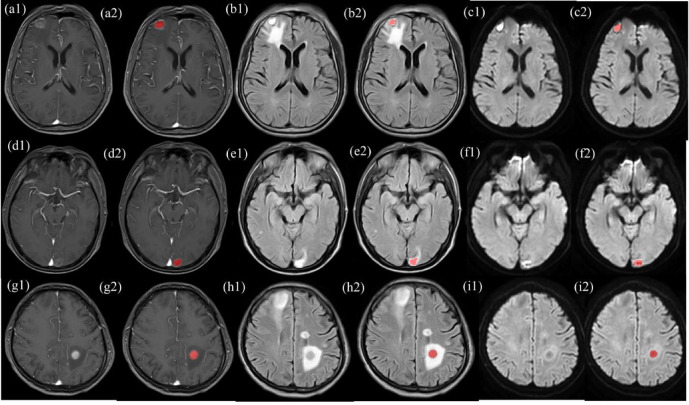

本研究旨在根据多参数磁共振成像(MRI)的放射组学特征,区分非小细胞肺癌(NSCLC)与小细胞肺癌(SCLC)的脑转移(BMs),以及腺癌(AD)与非腺癌(NAD)亚型。276例脑转移患者,其中98例为SCLC, 178例为NSCLC,按7:3的比例随机分为训练(193例)和测试(83例)数据集。178例NSCLC患者中,155例为原发性AD, 23例为NAD;这些患者也被随机分为训练(124例)和测试(54例)数据集。基于从对比度增强t1加权成像(T1CE)、t2流体衰减反演恢复(T2-FLAIR)和弥散加权成像(DWI)图像中提取的放射组学特征,采用Logistic回归分析构建分类模型。通过Delong试验、Hosmer-Lemeshow试验和Brier评分的校准曲线、精密度-召回率曲线和决策曲线分析来评价诊断效率。与来自单一序列的放射组学特征相比,基于T1CE、T2-FLAIR和DWI图像的多参数联合序列MRI放射组学特征在区分源自不同肺癌亚型的脑转移方面表现出更大的特异性。在训练和测试数据集中,该模型用于SCLC和NSCLC脑转移分类的auc分别为0.765 (95% CI 0.711, 0.822)和0.762 (95% CI 0.671, 0.845),而结合这三个序列的预测模型用于区分AD和NAD脑转移的auc分别为0.861 (95% CI 0.756, 0.951)和0.851 (95% CI 0.649, 0.984)。基于多个MRI序列组合的放射组学分类方法可用于鉴别各种肺癌脑转移。

This study was aimed at differentiating brain metastases (BMs) from non-small cell lung cancer (NSCLC) vs. small cell lung cancer (SCLC), and the adenocarcinoma (AD) vs. non-adenocarcinoma (NAD) subtypes, according to radiomics features derived from multiparametric magnetic resonance imaging (MRI). A total of 276 patients with BMs, including 98 with SCLC and 178 with NSCLC, were randomly divided into training (193 cases) and test (83 cases) datasets in a 7:3 ratio. Of the 178 patients with NSCLC, 155 had primary AD, and 23 had NAD; those patients were also randomly divided into training (124 cases) and test (54 cases) datasets. Logistic regression analysis was used to construct classification models based on the radiomics features extracted from contrast-enhanced T1-weighted imaging (T1CE), T2-fluid-attenuated inversion recovery (T2-FLAIR), and diffusion-weighted imaging (DWI) images. Diagnostic efficiency was evaluated with the area under the receiver operating characteristic curve (AUC) through Delong's test, calibration curves through the Hosmer-Lemeshow test and Brier score, precision-recall curves, and decision curve analysis. Compared with radiomics features derived from a single sequence, multiparametric combined-sequence MRI radiomics features based on T1CE, T2-FLAIR, and DWI images exhibited greater specificity in distinguishing BMs originating from various lung cancer subtypes. In the training and test datasets, the AUCs of the model for the classification of SCLC and NSCLC BMs were 0.765 (95% CI 0.711, 0.822) and 0.762 (95% CI 0.671, 0.845), respectively, whereas the AUCs of the prediction models combining the three sequences in differentiating AD from NAD BMs were 0.861 (95% CI 0.756, 0.951) and 0.851 (95% CI 0.649, 0.984), respectively. The radiomics classification method based on the combination of multiple MRI sequences can be used for differentiating various lung cancer BMs.